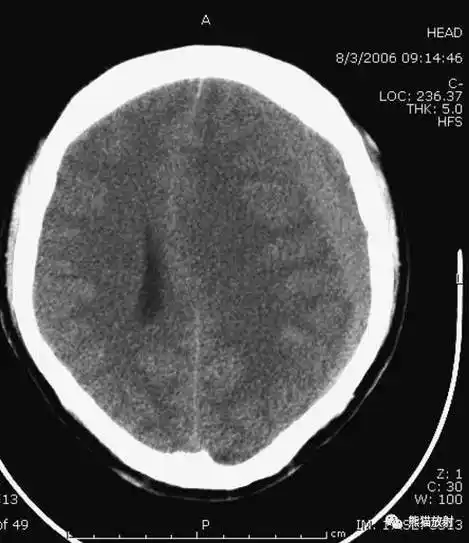

头颅ct扫描时如何打角度才能看得更多更清晰